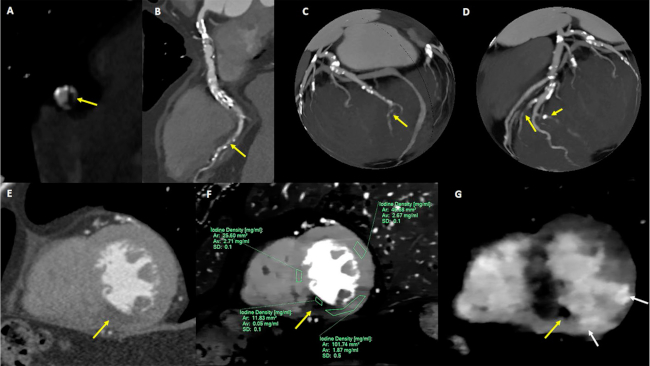

Caso 4. Se trata de un paciente de 68 años, diabético, tabaquista previo. Ingresó con hemiparesia izquierda de menos de 6 horas de evolución. Al ingreso se encontraba afebril, con una presión arterial de 184/112 mmHg, y una frecuencia cardíaca de 105 lpm. La RM de encéfalo evidenció una lesión cerebelosa y lentículo capsular del lado derecho de origen isquémico reciente e infiltración ateromatosa del tronco basilar, con estenosis moderada; y ateromatosis difusa no significativa de otros territorios. Se procedió a realizar una angiografía digital cerebral, y se observó ateromatosis difusa y estenosis de leve a moderada de la arteria basilar. Se decidió realizar tratamiento médico. El ECG demostró bloqueo completo de la rama derecha y hemibloqueo anterior, con alteraciones inespecíficas de repolarización. No presentó evidencia de trastornos de la motilidad en el ecocardiograma transtorácico. El laboratorio informó elevación de enzimas y curva; se decidió realizar una cinecoronariografía, donde se evidenció ateromatosis difusa, con múltiples lesiones graves de aspecto trombótico en las ramas secundarias; se decidió implantar un stent en el tercio distal de la coronaria derecha. Se realizó una TC cardíaca (Figura 4) para descartar FCE. Se observó ateromatosis difusa, que incluía lesiones oclusivas en las ramas descendente posterior, lateroventricular, y diagonal. En la arteria coronaria derecha se observó un aneurisma a nivel del tercio medio, con trombosis mural excéntrica no obstructiva. Además, en el análisis espectral, se identificó un grave defecto de perfusión inferior, con realce tardío de contraste de patrón transmural y con evidencia de obstrucción microvascular (“no reflow”, Figura 4 F-G). Se calculó un VEC septal de 38%, y un VEC de 68% a nivel del área lateral con máximo realce.